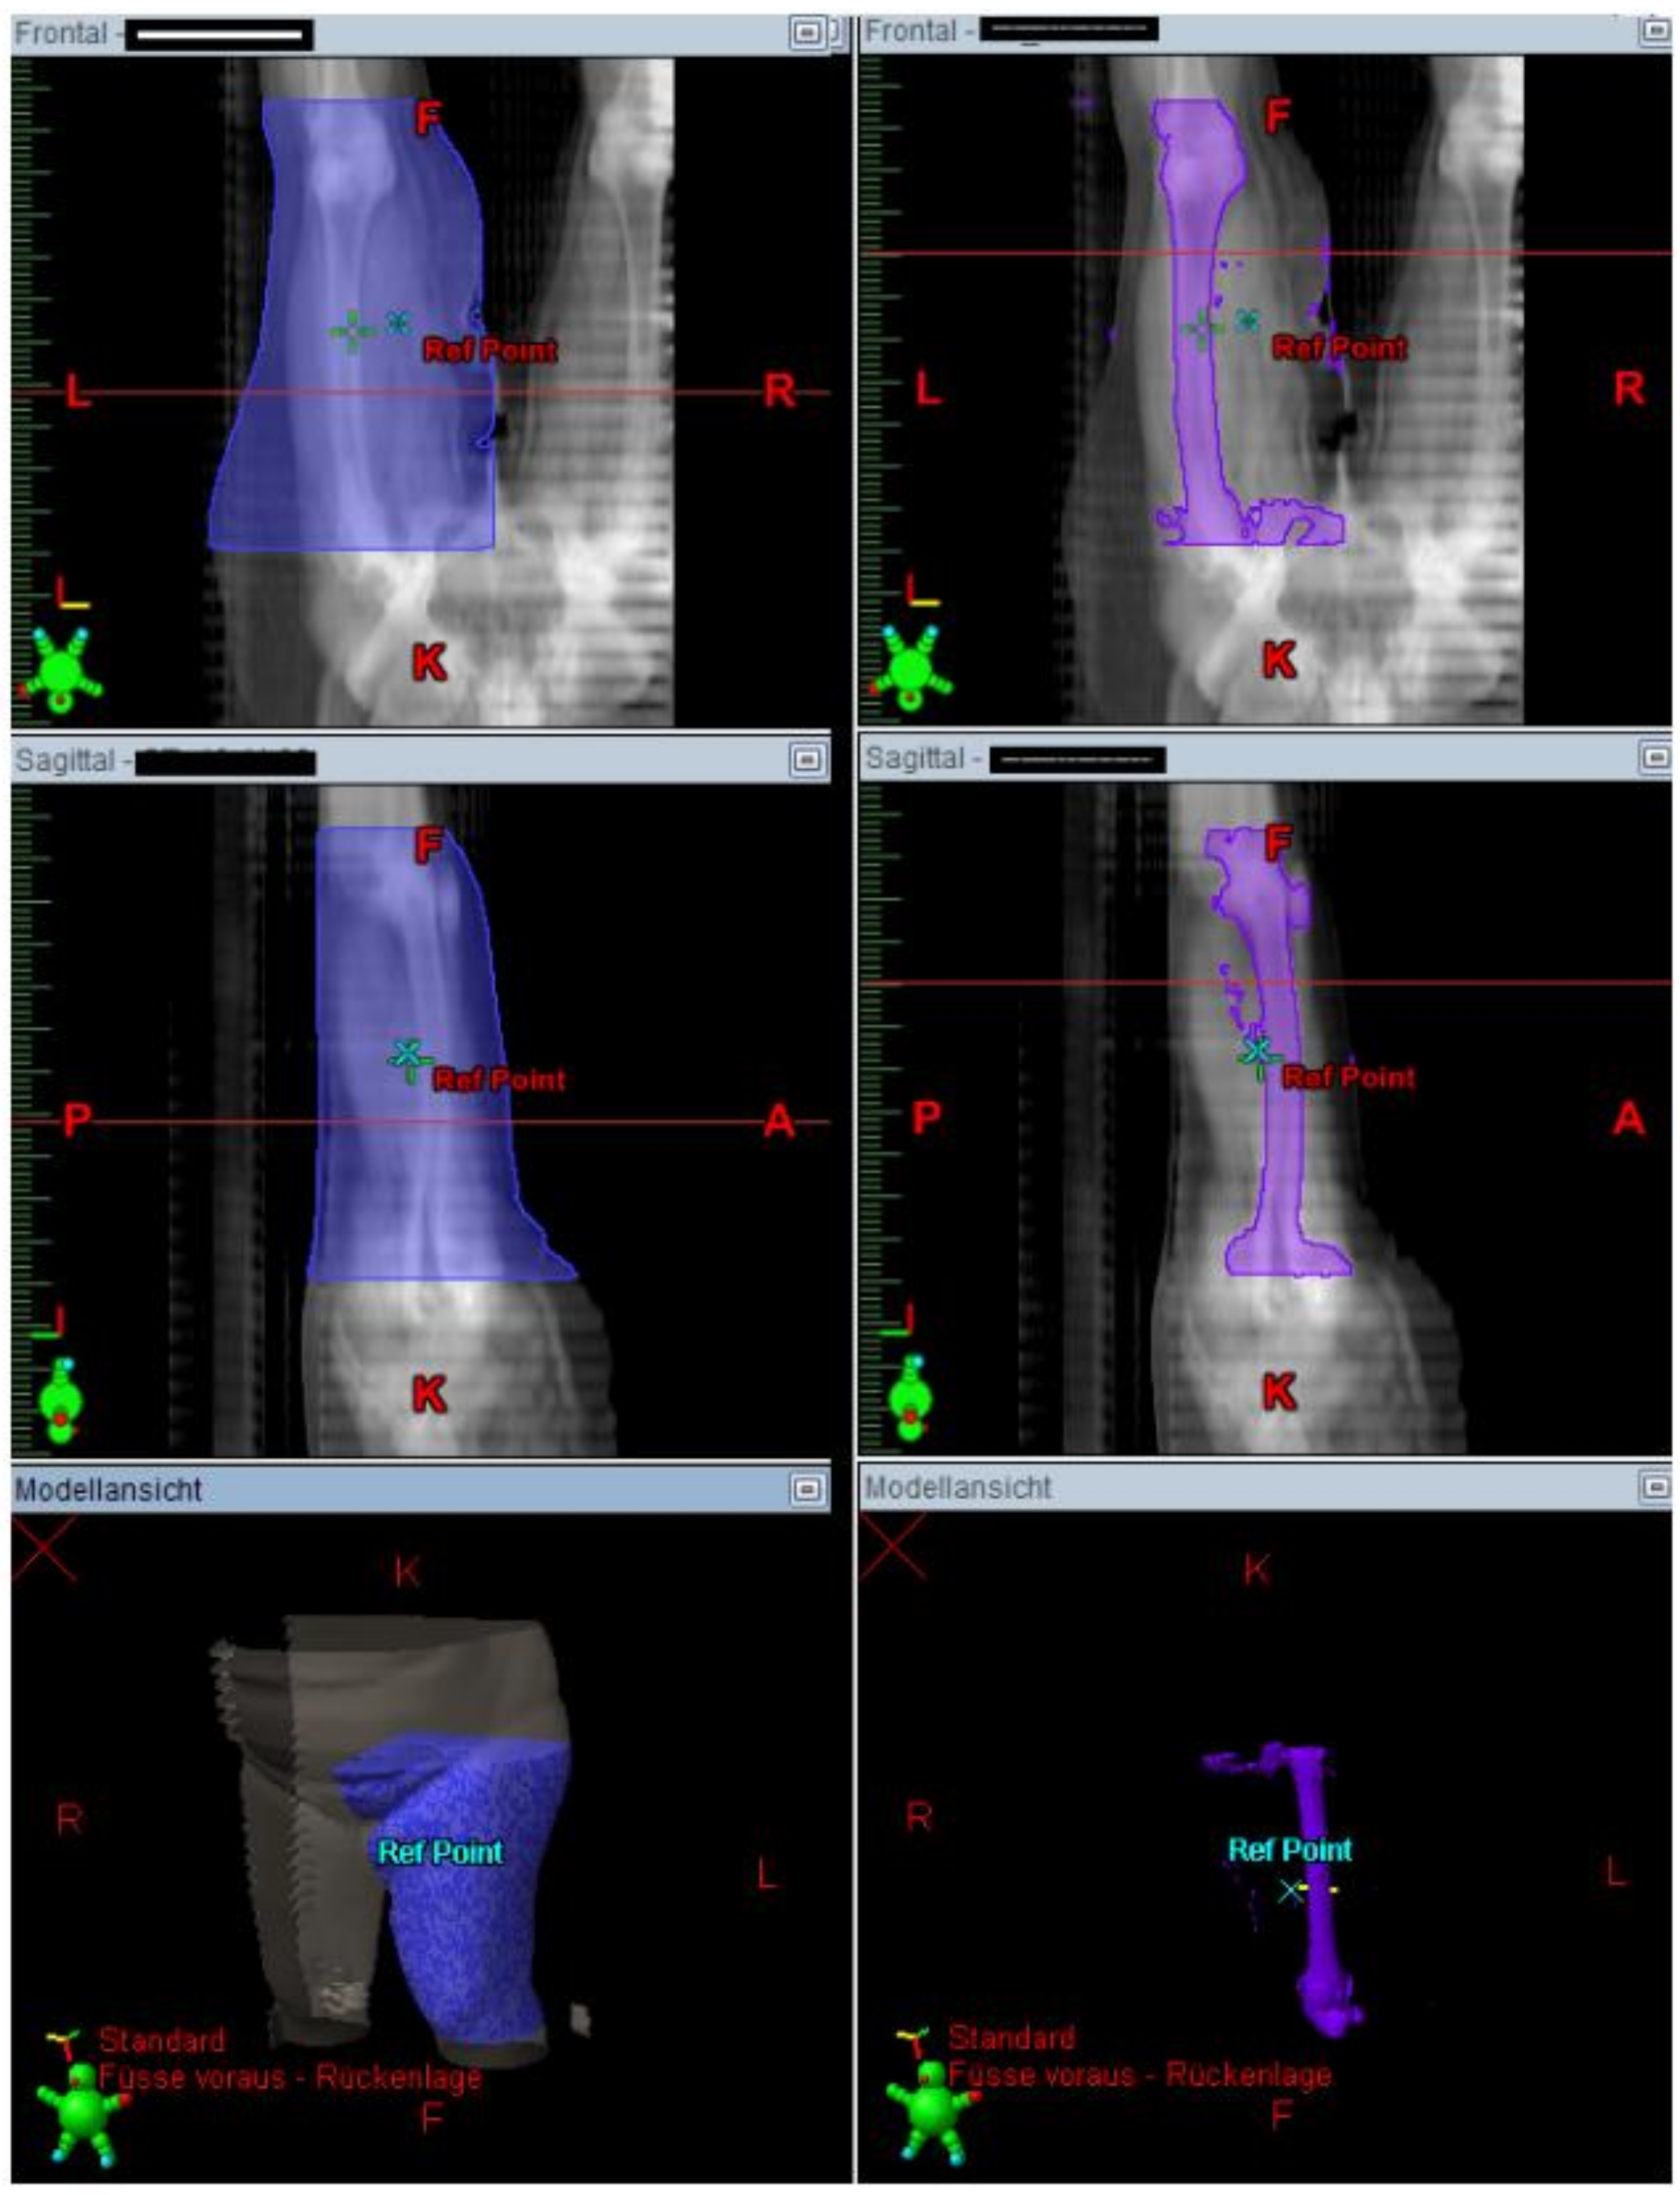

The irradiated part of the extremity was demonstrated in the radiation plan including the isodose lines to confirm a continuous lymph-sparing volume outside the 20% isodose level. If a boost was applied, the plan sum was considered. Depending on the extent of the radiation field, the extremity was defined from the middle of the ankle joint up to the hip joint or from the radioulnar joint up to the shoulder joint, respectively. The extremity and the continuous lymph-sparing volume were created as a 3D structure in the planning CT. In a few parts of the extremity the lymph-sparing volume was narrower due to anatomical and disease-specific reasons (Figure 1 and Figure 2). Bone volume was subtracted from the extremity volume (Figure 3 and Figure 4). The narrowest 10 cm of the lymph-sparing volume was also defined as a 3D structure (Figure 5).

Figure 3.

3D contouring of the extremity and bone to prepare bone subtraction from the extremity volume.

Figure 4.

Subtracting the bone volume from the extremity volume.

Figure 5.

Contouring the area of the narrow lymph-sparing volume with 10 cm length.

The next step was to calculate the proportion of the lymph-sparing volume in relation to the extremity volume. The same was done with the narrowest part of the lymph-sparing volume, which was double weighted in the formula for the lymph-sparing quotient (Figure 6).

Figure 6.

Calculating the volume receiving 20% of the dose in DVH (LSV) in the whole extremity (blue) and the narrowest part of the lymph-sparing volume (yellow).